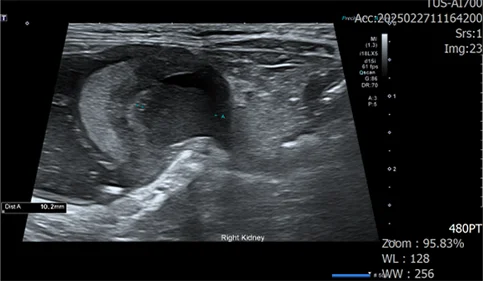

• 세균성 신우신염 및 신장파열 환자

식욕 부진과 체중 감소로 내원한 환자입니다.

혈액 검사상 WBC 상승, 신장 수치 상승, 심각한 수준의 전해질 불균형이 확인되었습니다.

우측 신장 주변부 가스, 복수, 신장의 형태 변화, 신우의 확장, 요관 확장 확인

신우내 저류하는 액체 천자 진행, 점액성 농이 다수 확인

도말 상 세균 확인

정밀 검사 결과, 신장 주변 가스, 복수, 신장 파열이 확인되었습니다.

세균성 신우신염으로 인한 신장 파열이 발생, 그로 인한 이차적인 복막염으로 진행되는 상태입니다.

즉시 우측 신장절제 수술을 진행했으며, 입원 기간 동안 쇼크와 빈혈 등 수많은 응급 상황이 발생했으나 매 순간 적절한 처치와 항생제 치료를 통해 환자 상태가 호전되었습니다.

15일 만에 신장 수치 정상화 후 무사히 퇴원했습니다.